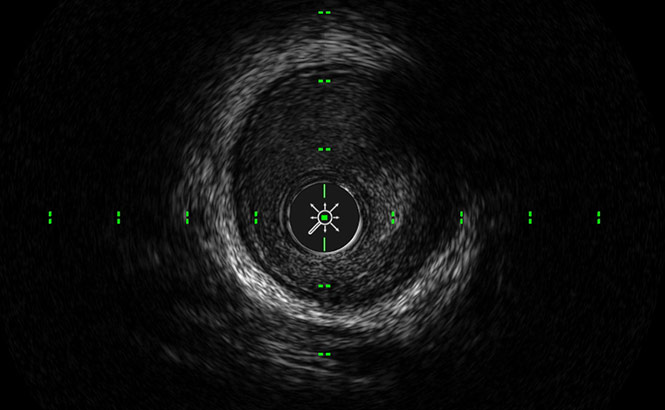

ACIST HDi High-Definition IVUS System enables optimized visualization to inform and illuminate coronary and peripheral intervention strategy through advanced imaging modes, improved deliverability of the Kodama IVUS Catheter and interactive compact console.

LumenView™

Darkens the coronary lumen for better border detection.

SilkView™

Increases gray scale for finer blood speckle, tissue and plaque differentiation.

ClassicView™

Optimizes the balance of high resolution and depth of penetration and enables full vessel wall visualization.